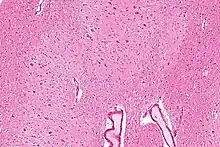

![]() Sagittal section through right cerebellar hemisphere. The right olive, "inferior olivary nucleus", has also been cut sagittally – from front to back. (Dentate nucleus, "nucleus dentatus", labeled at top.) | |